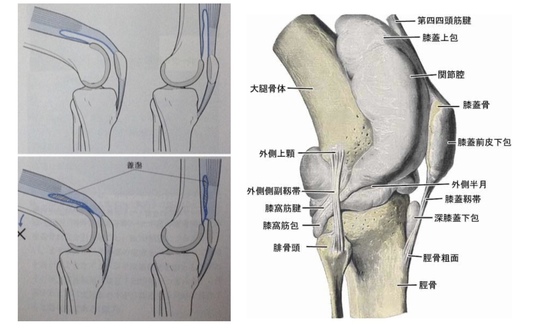

歩行時の筋電図 引用

ここに歩行時の筋電図があります。

イラストをみるとわかるように、歩いているときに大腿四頭筋はどれほど使われているでしょうか!

TVなどでは、膝痛には大腿四頭筋だ!

と言われますが、ハムストリングスの方が活動量としては多いように感じます。

だから、ハムストリングスが1番大切だ!

と安易に考えてはいけません。

全ての筋肉に役割があり、それぞれの機能があるからこそキレイに動くことができます。

要するに、大腿四頭筋だけを鍛えても何も変わりません。

1、膝関節の動きには、『転がり』と『滑り』があり、この動きを作る

2、半月板と接しているハムストリングスと腓腹筋の可動性を作る

3、ハムストリングスの収縮により半月板が動く膝を作る

4、大腿四頭筋と水固まる場所(膝蓋上鵬)の組織間の滑りを作る

この4つがキーポイントになります。